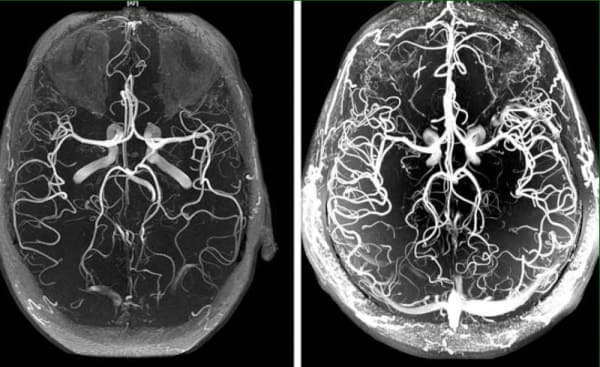

Церебралната ангиодистония на мозъчните – съдове е патологично състояние, при което съдовият тонус и нормалният кръвоток в мозъчната тъкан са нарушени. В тази статия можете да прочетете за причините, механизмите и симптомите, на които следва да се обърне сериозно внимание. Освен това ще научите за сериозните усложнения на това коварно заболяване и за съвременния подход към лечение, достъпен за всички.

Церебралната ангиодистония на мозъчните съдове оказва влияние върху функционирането на целия организъм. Поради недостатъчното кръвоснабдяване на мозъка общата работоспособност намалява, появява се усещане за слабост, нарушават се функциите на важни системи в организма.